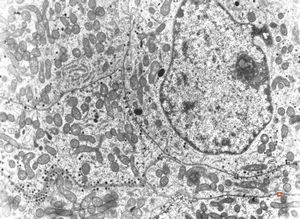

M, 62y. | pheochromocytoma